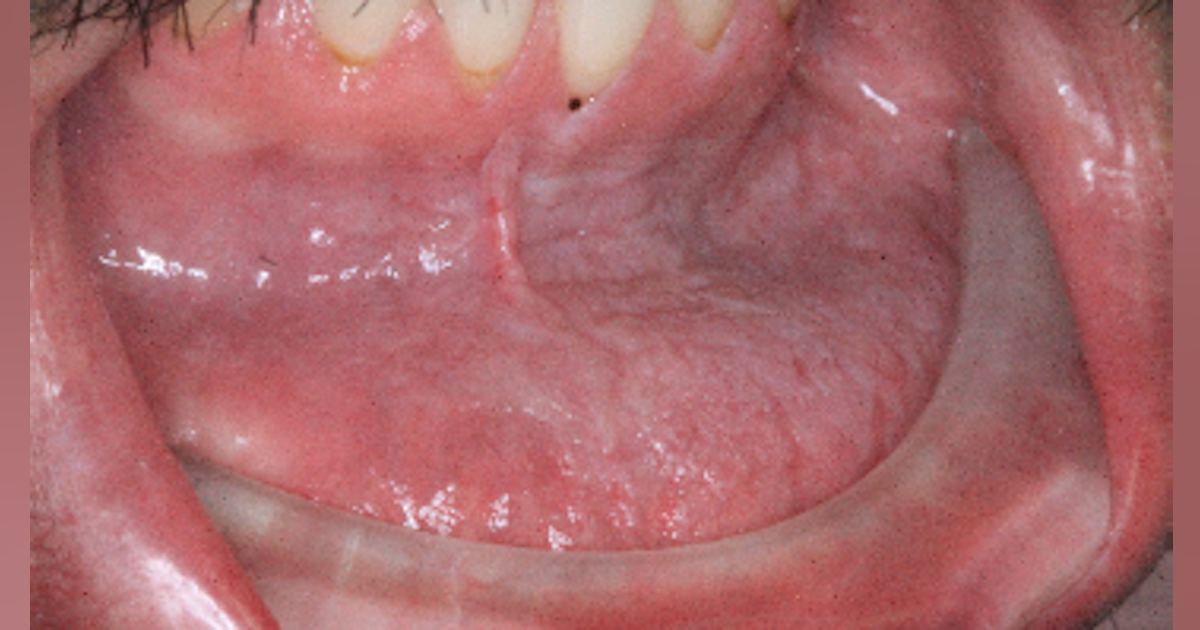

Diagnosis And Treatment For Breakthrough Clinical Oral Pathology Case

Diagnosis and treatment for Breakthrough Clinical oral pathology case www.dentistryiq.com

Breakthrough Clinical Oral Pathology Case: No. 29 | Dentistry IQ

Breakthrough Clinical oral pathology case: No. 29 | Dentistry IQ www.dentistryiq.com